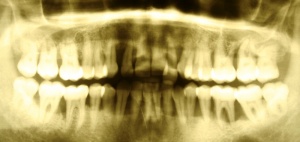

[Abb-2]In den vergangenen zehn Jahren wurden circa 34.000 Implantate durch das SanABw bzw. das KdoSanDst UA III genehmigt. Wenn die von Roos-Jansacker publizierte Prävalenzrate von 6,6 % zugrunde gelegt wird, müsste zwischenzeitlich an circa 2250 Implantaten eine Periimplantitis diagnostiziert worden sein. Zitzmann et al. geben eine Rate von 28 % periimplantäre Entzündungen an. Dies bedeutet, dass circa 9500 Implantate eine Mukositis bzw. Periimplantitis aufwiesen bzw. aufweisen.

In der prächirurgischen Phase muss ein besonderes Augenmerk auf die prognostische Einschätzung der parodontalen und dentalen Situation gelegt werden. Dabei ist insbesondere auf die allgemeinmedizinische und spezielle dentale Anamnese zu achten. Bornstein et al. (2009) untersuchten den Einfluss von Allgemeinerkrankungen auf die Periimplantitis. Unter anderem Safi et al. (2009) wiesen auf die Bedeutung einer Parodontitishistorie hin. Aber auch die Lebensgewohnheiten des Patienten haben einen entscheidenden Einfluss (Tabakkonsum, ungenügende Mundhygiene, fehlende Nachsorge [Heitz – Mayfield & Huynh – Ba 2009]) (Abb. 3).

Diagnostische Parameter für die Beurteilung der dentalen und der periimplantären Zustände sind die Plaqueakkumulation, die Sondierungstiefen des Zahnes und des Implantates, Bluten auf Sondierung, Suppuration und der radiographische Knochenverlust (Salvi & Lang 2004). Unabdingbar ist im Minimum eine Sechspunktmessung (Sondiertiefen und klinischer Attachmentlevel). Immer wieder hört man von der Befürchtung, dass durch ein Sondieren des Implantates dieses geschädigt wird. In einer histomorphometrischen Studie an Hunden haben Etter et al. (2002) die Heilung des periimplantären Weichgewebes nach standardisiert klinischem Sondieren untersucht. Die Heilung des Epithelansatzes nach Sondierung des gesunden periimplantären Gewebes ist nach fünf Tagen abgeschlossen. Erfahrungsgemäß ist bei besonders aufmerksamem und vorsichtigem Sondieren ein äußerst geringes Verletzungsrisiko gegeben. Auch diese Techniken können in einem Praktikum bei einem Parodontologen aufgefrischt werden.